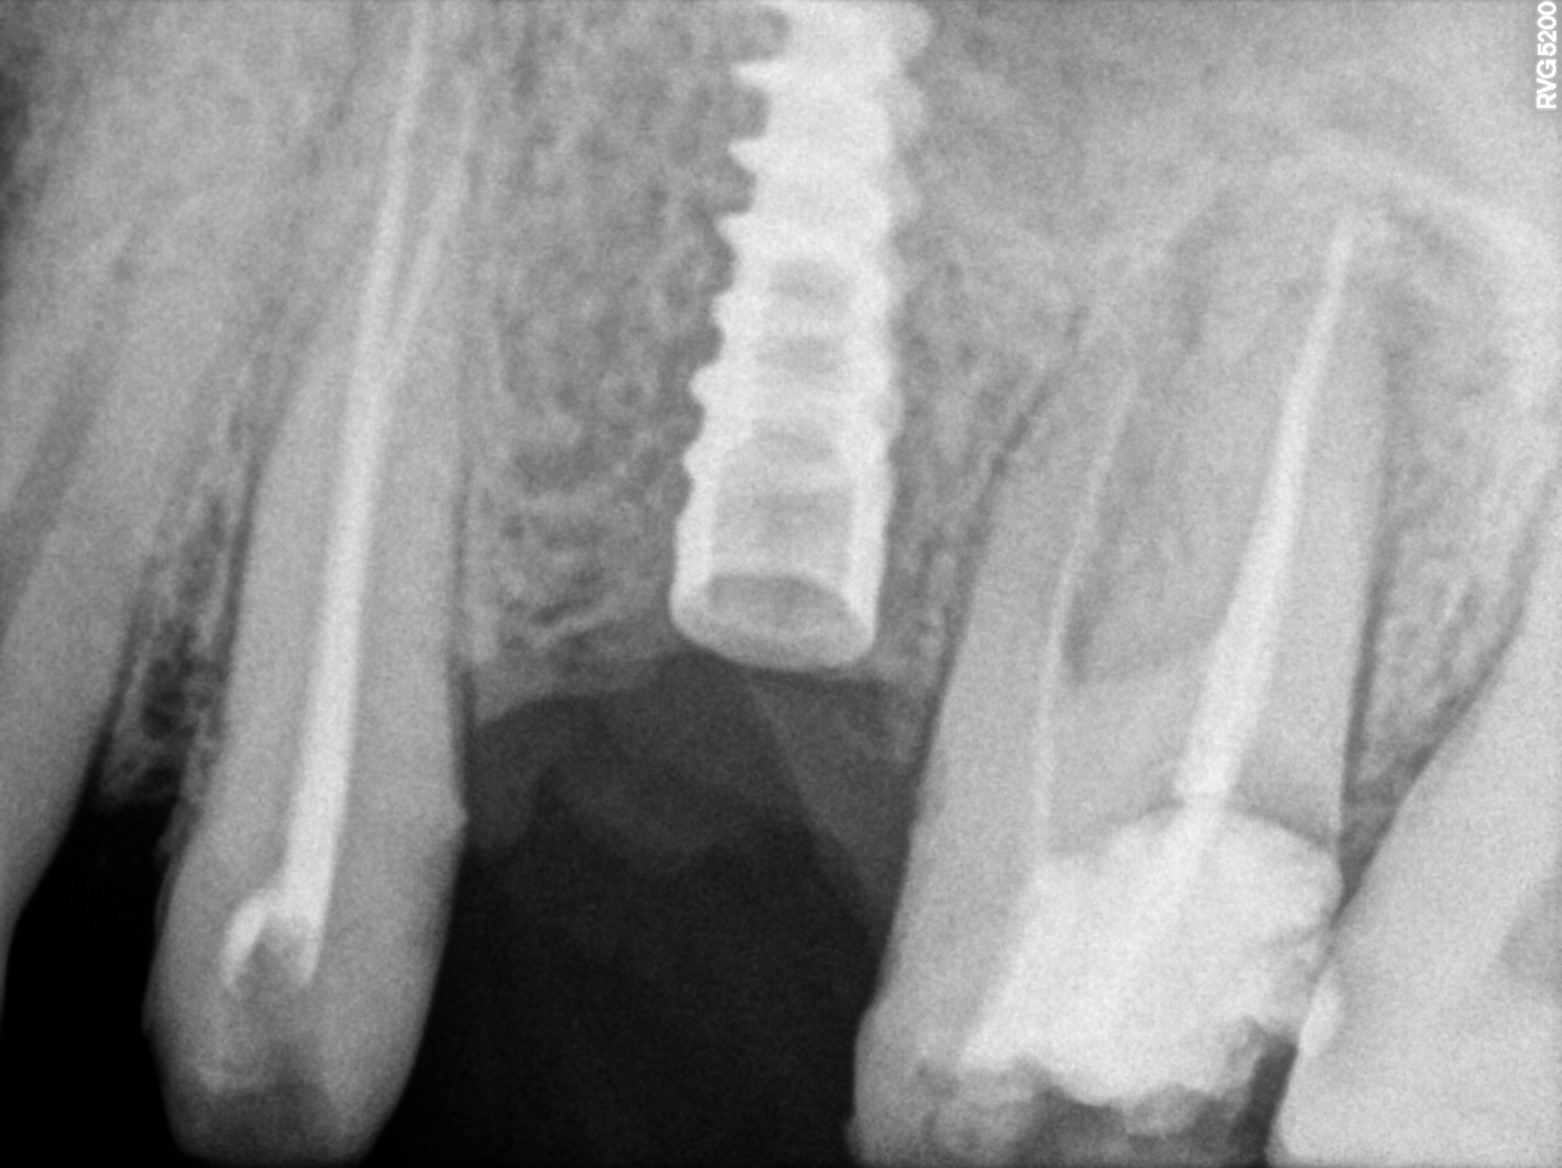

Dental Radiographs FHIR: DocumentReference · LOINC 24641-7

R53 (2).jpg

24641-7

R55.jpg

xray_1773475755_1.jpg